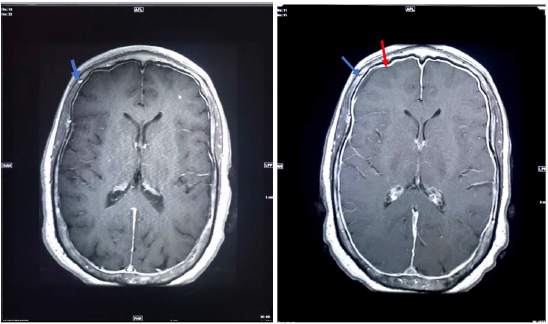

Traditionally, MRI of the brain and spinal cord with and without contrast have been the imaging studies of choice when a spontaneous CSF leak is initially suspected. Prominent abnormal features including meningeal enhancement, sagging of the brain, and/or engorgement of cerebral venous sinuses on brain MRI (Figure 1,2 & 3) or extra-arachnoid fluid collections, collapse of the Dural sac, or extradural extravasation of fluid on spinal MRI (Figure 4) may all be suggestive of a CSF leak [5-9]. If the leak can be adequately localized using MRI, an epidural blood patch is used to repair the leak. If the initial blood patch is unsuccessful a CT myelogram is performed to better localize the problem area and repair with an epidural blood patch is once again attempted. The difficulty of locating the site of a spontaneous CSF leak is that 30- 40% of patients diagnosed will have leaks from multiple sites [4]. Furthermore, it has been noted that MRI imaging in patients with a suspected leak remains normal 20% of the time [1]. Spontaneous CSF leaks sometimes resolves spontaneously within weeks or years leaving patients with intermittent orthostatic headaches. Most, however, require multiple blood patches before culmination, and data suggests that 10% of patients will relapse regardless of treatment [1].

Figure 1:A comparison of an axial T2 weighted MRI brain of patient one month apart. a) Taken at first presentation of headache and shows dura tightly adhered to the calvarium and bridging veins tight against calvarium (blue arrow). b) Taken one month after initial presentation. Shows thickening of the meninges and pachymeningeal enhancement (red arrow) seen as a white ring surrounding the brain. Also shows bridging veins separating from calvarium (blue arrow).